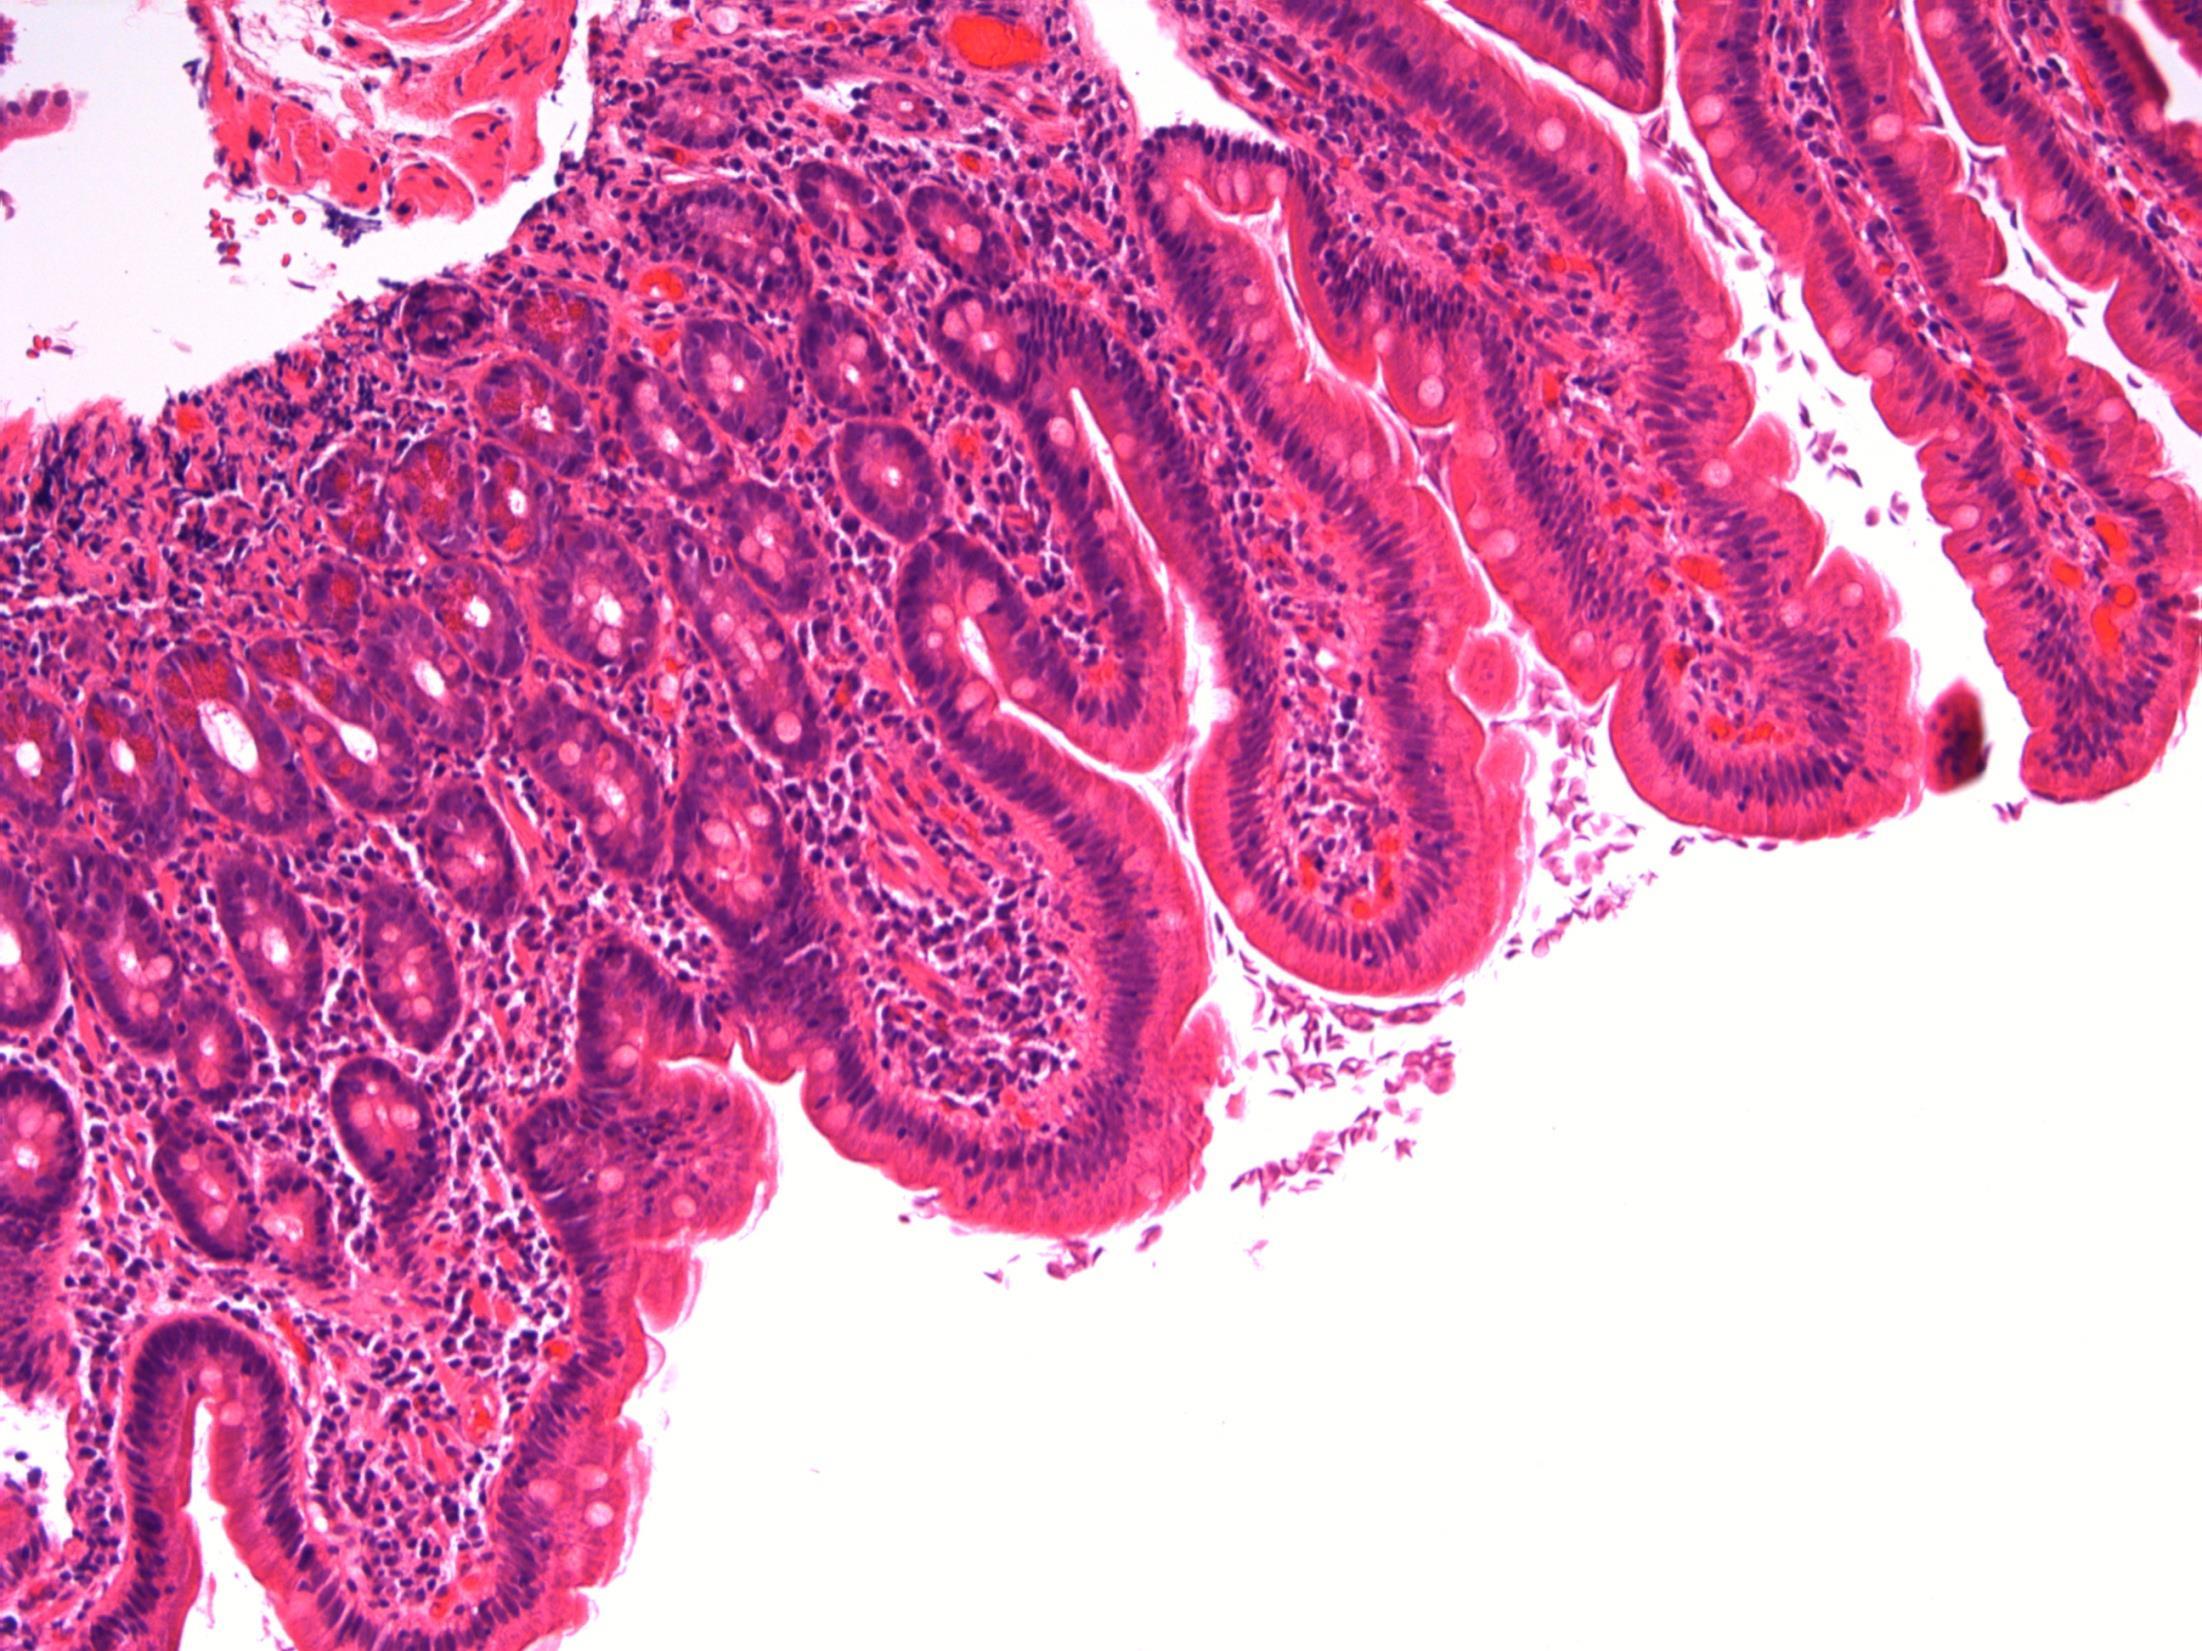

71F. Abdominal pain and diarrhoea. Upper GI endoscopy normal. D2 biopsy taken to exclude coeliac disease

Duodenum - Giardiasis

Giardiasis

Description: Small bowel mucosa of normal architecture. Trophozoites along the surface of epithelial cells. The organisms are teardrop/pear/comma shaped with paired nuclei. No evidence of malignancy. No evidence of coeliac disease.

Diagnosis: Giardiasis.

Plan: Correlate with clinical/travel history

Protozoan infection associated with malabsorption and chronic diarrhoea (this lady had diarrhoea).

Spreads by faecally contaminated water, usually underdeveloped countries ( hence travel history important).

3.5 Clinical features and associations 3.0 Justification of diagnosis; exclude coeliac disease 2.5 Description with diagnosis 2.0 Other non-neoplastic diagnosis with mention of giardia 1.5 Other non-neoplastic diagnosis with no mention of giardia 1.0 Neoplastic diagnosis